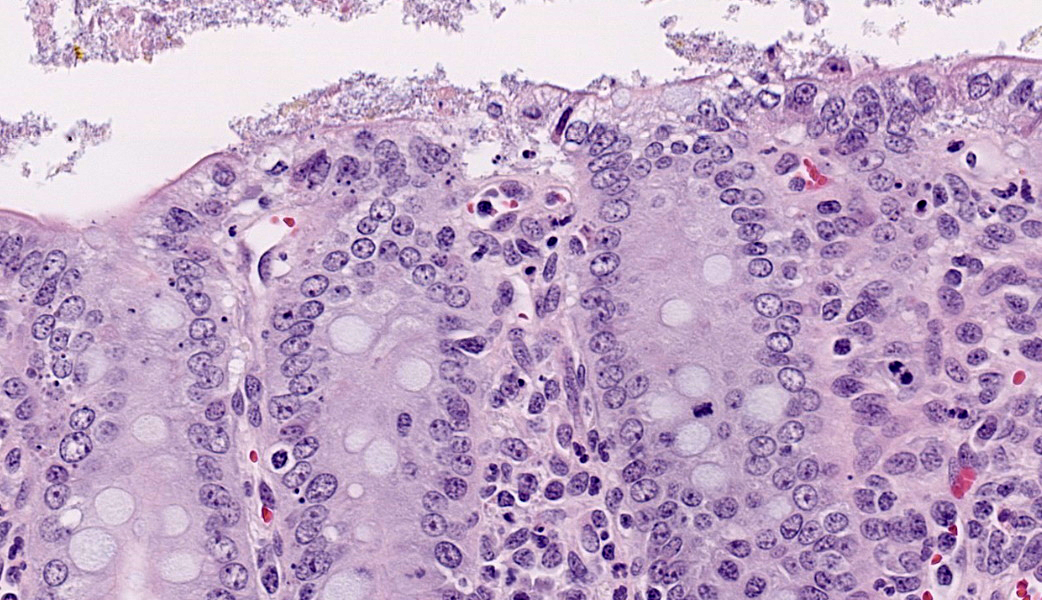

Ileum: In several sections, there is moderate multifocal blunting and fusion of villi with a crypt: villus ratio of 1:1. Apical enterocytes are often moderately attenuated with loss of the brush border and reduced apical cytoplasm. In some sections, these cells have a profound number of intracellular but extracytoplasmic 1-2 um circular eosinophilic apicomplexan organisms with 0.5 um basophilic nuclei (Cryptosporidium sp.). In other sections, these cells contain numerous larger apicomplexans with varied life-stages apparent including: 10 x 5 um curvilinear binucleate meronts (type I meronts), 4 x 12 um curvilinear uninucleate merozoites (type I merozoites), 9 x 6 um ovoid multinucleate meronts (type II meronts), multiple 3 x 12 um curvilinear uninucleate merozoites joined at their base by a residual body (type II merozoites), a 12um diameter circular lightly basophilic microgamont filled with numerous peripheral uninucleate deeply basophilic microgametes, or a 18 um diameter circular lightly basophilic macrogamont with a 8 um granular circular nucleus (macrogamont) (Cystoisospora suis). Rare crypts are ectatic, lined by moderately flattened, attenuated epithelium, and filled with cellular and karyorrhectic debris admixed with rare degenerate neutrophils (crypt abscesses). The associated lamina propria is often infiltrated by numerous eosinophils admixed with a few neutrophils. In one section, there is profound necrosis in Peyer’s patches, characterized by abundant karyorrhectic and cellular debris admixed with rare neutrophils, that often obscures typical follicular architecture. Similar changes are occasionally present in the overlying lamina propria, with marked lymphocytolysis and loss of proprial architecture. Vascular structures in all tunics are moderately congested, and macrophages occasionally aggregate around medium-caliber vessels in the submucosa.Spiral Colon: In both sections, there is moderate multifocal ulceration of the colonic mucosa characterized by loss of apical colonocytes with abundant cellular and karyorrhectic debris admixed with minimal fibrin and extravasated erythrocytes adhered to the exposed lamina propria. Adjacent colonocytes are often flattened, irregularly spaced, with reduced apical cytoplasm (attenuation). The associated lamina propria is often infiltrated by neutrophils and eosinophils admixed with necrotic debris and a few macrophages. Crypts within these areas are often ectatic, lined by mildly attenuated epithelium, and filled with either cellular and karyorrhectic debris admixed with degenerate neutrophils (crypt abscesses) or numerous eosinophils. Several other crypts are filled with up to 15 5 x 7 um pyriform to crescent-shaped protozoa with lightly basophilic cytoplasm and a faint nucleus (Suspect Trichomonads). The colonic lumen contains abundant cellular debris admixed with numerous colonies of basophilic bacteria with morphology ranging from coccoid to bacillary to filamentous, as well as rare 80 um circular flagellated protozoa with a prominent bean-shaped nucleus and a large cytoplasmic vacuole and abundant phagocytosed cellular debris (Suspect Balantidium coli). The submucosa is multifocally infiltrated by numerous macrophages admixed with lymphocytes and a small amount of karyorrhectic debris and these cells often aggregate around medium to large caliber vessels. Multifocally the cortical and medullary architecture of the mesenteric lymph node is effaced by abundant cellular and karyorrhectic debris (lymphocytolysis) admixed with rare infiltrating neutrophils and macrophages.

Ileum and colon (mediastinal lymph node, Peyer’s patches, and lamina propria): Lymphoid necrosis, multifocal, profound, subacute.Ileum: Atrophic enteritis, necrosuppurative and eosinophilic segmental, marked, subacute, with crypt abscesses and numerous intralesional apicomplexans with morphology consistent with Cryptosporidium spp. and Cystoisospora suis

This is great example of a real-world production animal diagnostic case. It’s also a great reminder to look for a primary etiology when there are multiple organisms/changes present in a piece of tissue that aren’t typically seen together. Cryptosporidium suis and scrofarum are present in many commercial pigs but typically do not cause clinical disease and are generally not histologically apparent.8,13 The presence of such profound quantities of Cryptosporidium spp. in this case suggests primary immune suppression. The larger apicomplexan present in this slide has life stages that are morphologically consistent with Cystoisospora suis. While this organism can act as a primary enteric pathogen in pigs, it is also present at low levels in many commercial swine post-weaning without causing clinical disease, often with few if any histologically apparent life-stages. The presence of both types of meronts, both types of merozoites, as well as microgamonts and macrogamonts in a single section of tissue is unusual and also suggests that primary immune suppression may be at play. Lindsay et al. did a great job describing these life stages in a in 1980 Journal of Parasitology paper.7 The moderate ulcerative colitis in this animal is typical of a Salmonella spp. It’s also common to have Balantidium coli find their way into these colonic lesions, often phagocytosing necrotic debris.9,13 The pyriform organisms in the colonic crypts are morphologically consistent with trichomonads. Tetratrichomanas foetus, suis,buttreyi, and Pentatrichomonas hominis have all been described as inhabitants of the porcine digestive tract. Others are likely present in pigs, and there have been increased efforts, especially in China, to better characterize these organisms.6 They are commonly seen in higher numbers in porcine colonic crypts during disease or dysbiosis.PCV-2 parasitizes lymphocytes and is a common cause of immune suppression in commercial pigs. However, this virus typically causes lymphoid depletion with granulomatous inflammation and rarely intracytoplasmic botryoid inclusion bodies. PCV-2/3 differential PCR was negative in this animal. The massive amount of karyorrhectic debris in the lymphoid tissue is more in line with PRRSV infection, which was detected at a very low CT in lung, and colocalized to the lesioned enteric lymphoid tissue by IHC. PRRSV is a member of the family Arteriviridae, which together with Coronaviridae, Roniviridae, and Mesonoviridae form the order Nidovirales, a contemporarily relevant viral order that has evolved a unique replication strategy utilizing discontinuous extension and a set of nested subgenomic mRNAs. The economic impact of PRRSV in the US is estimated to be $660 million annually, and a reasonable case could be made that this is the most economically important virus of any domestic species in the US.3 PRRSV replicates in macrophages and, to a lesser extent, dendritic cells. There was much historical controversy about the receptor utilized by this virus for cell entry. In a landmark paper, Prather et al. were able to demonstrate complete resistance to the virus by knocking out CD163 in commercial pigs with CRISPR/Cas9 methods.11 CD163 (HbSR) is a hemoglobin scavenger receptor that is expressed in cells of the monocyte-macrophage lineage.1 Currently, CD163 knock-out pigs are working their way through the federal regulatory system, with the genetics company involved hoping to market a completely PRRSV resistant animal. This may have huge economic implications given the limited success of commercial vaccines against this phylogenetically diverse virus. While this virus is classically associated with interstitial pneumonia with intralesional “necrotic macrophages”, it’s a systemic pathogen that can infect macrophages in any body system, especially lymphoid tissue. The terms “necrotic macrophages” and “lymphoid necrosis” are somewhat controversial in PRRSV infection. An early paper utilizing tunnel assays, demonstrated widespread apoptosis of noninfected cells in the lung, testes, and lymphoid tissue, giving rise to the idea of “bystander-apoptosis” involvement in the pathogenesis of this virus.10 Subsequent papers further characterizing the involvement of intrinsic/extrinsic/other apoptotic pathways in infected and uninfected cells are conflicting.2 At the very least it can be stated that much of the cell death in a PRRSV infection occurs in uninfected cells, and a significant proportion of those cells are likely apoptotic as opposed to necrotic.

- Ileum: Villar blunting, diffuse, marked with numerous intracytoplasmic, extracellular apicomplexan schizonts and gamonts consistent with Cryptosporidium sp., and intracytoplasmic, intracellular apicomplexan meronts, schizonts, and gamonts consistent with coccidiosis.